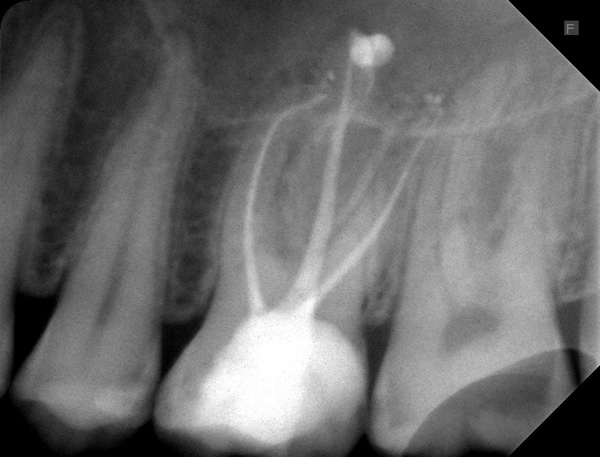

Wir haben die Wurzelkanalbehandlung in einer Sitzung durchgeführt. Das Kontrollröntgenbild der Wurzelkanalfüllungen: